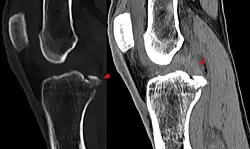

Röntgenaufnahmen leisten keinen unmittelbaren Beitrag zur Diagnosestellung einer Kreuzbandruptur. Beide Kreuzbänder sind – ob gerissen oder nicht – im Röntgenbild nicht sichtbar. Wird dennoch geröntgt, so kann dies der Diagnosestellung von möglichen knöchernen Begleitverletzungen dienen.

Sonderfall knöcherner Ausriss

Der knöcherne Ab- oder Ausriss des vorderen Kreuzbands vom Knochen (Schienbein oder Femur) ist wesentlich seltener als seine intraligamentäre Ruptur[255] und ist definitionsgemäß kein Kreuzbandriss. Dieser Sonderfall tritt häufiger bei Kindern, vor allem im Bereich des Kreuzbandansatzes am Schienbein Eminentia intercondylica auf und hat durch Refixierung des Ausrisses – beispielsweise mit Schrauben oder Drahtnaht – allgemein gute Chancen, wieder vollständig knöchern einzuheilen. Bei der arthroskopischen Refixation der das Kreuzband tragenden Knorpel-Knochen-Schuppe ist eine gute Übersicht von entscheidender Bedeutung, um die Einklemmung des Ligamentum transversum genus (zwischen den Menisken) unter dem Fragment zu vermeiden. Ansonsten ist die Mini-open-Technik vorzuziehen. Generell ist darauf zu achten, mit den Implantaten (Schrauben oder Drahtnähten) die Wachstumsfuge nicht zu blockieren.